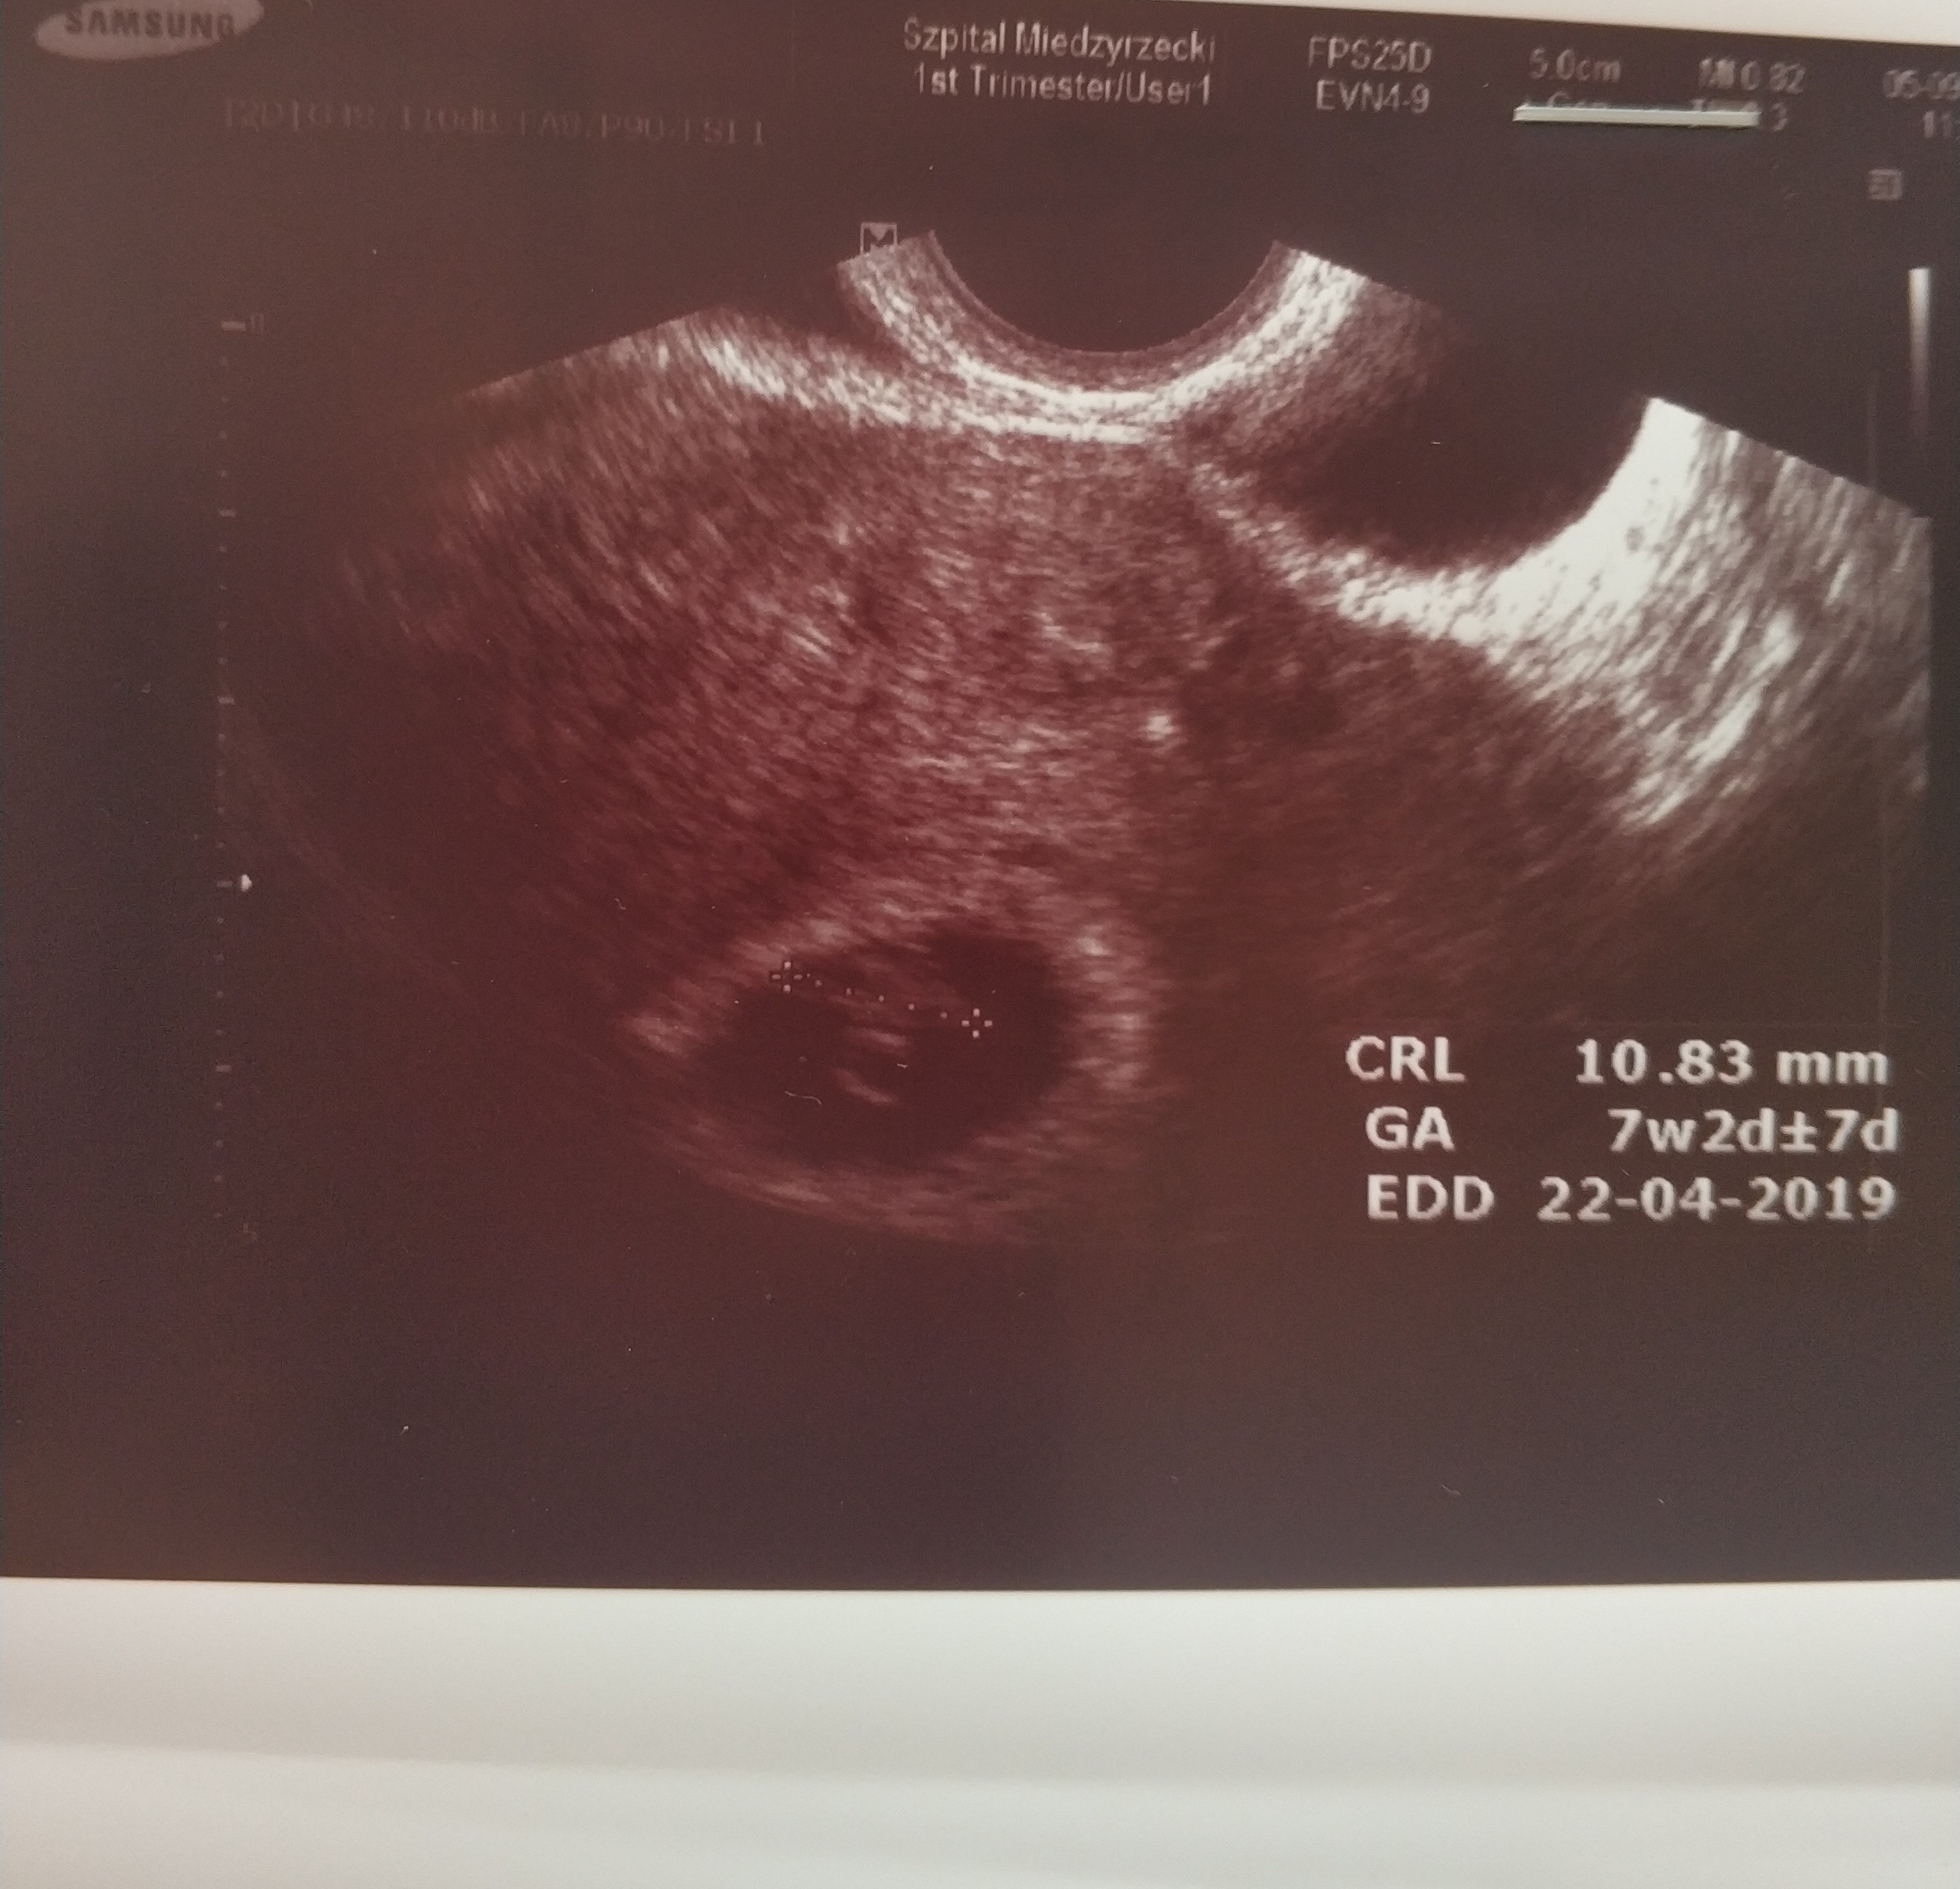

Jest moj mały cudowny kropeczek mierzy 11mm! i widzialam pieknie bijace serduszko. co za widok

zycze kazdemu tego doswiadczyc. Ciaza zywa prawidlowa wszystko w jak najlepszym porzadku.

lekarz super.. tak sie balam tej wizyty i jego docinek a tymczasem byl mega profesjonalny i wykazal sie wzgledem mnie wysoką kulturą osobistą. Ale może hajs tak na niego dziala nie wiem... mam watpliwosci na kogo sie zdecydowac.. tego mojego poprzedniego czy tego nowego ktory jest ordynatorem u nas na oddziale. Termin porodu przeskoczyl mi na 22 kwietnia. Wg OM mam 7+3 wg USG 7+2.

zalaczam zdj mojego kropeczka.